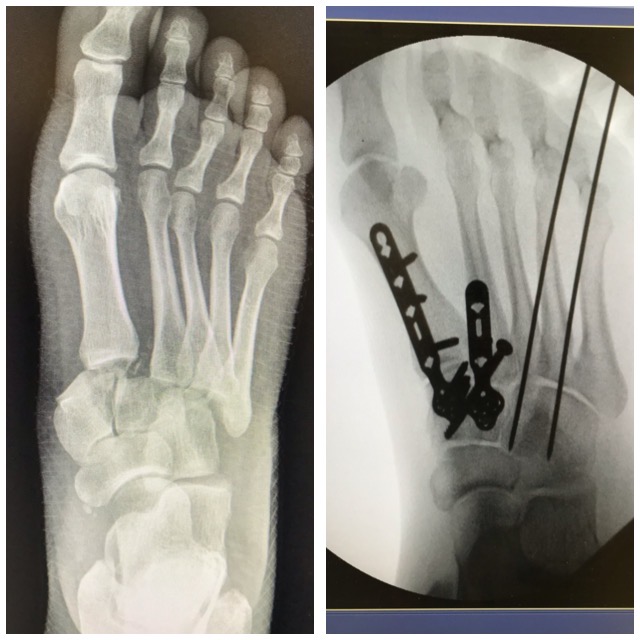

Jalkaterämurtuma

Ennen – jälkeen